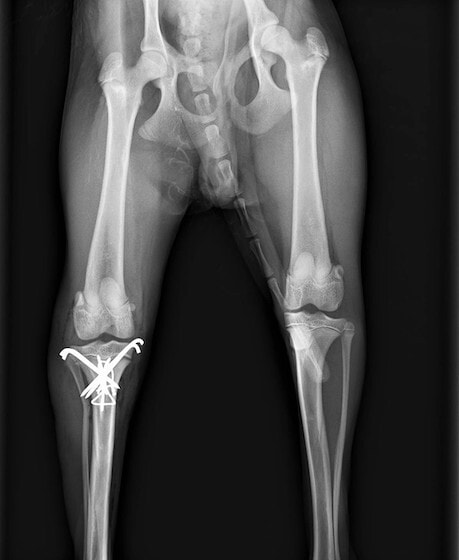

症例3:キルシュナーワイヤーのピンニングによる整復

ペルシャ猫 11ヶ月齢 雄

他院にて左大腿骨遠位の成長板骨折(salter-harrisⅠ型)が認められており、治療相談を目的として来院。当院にて、キルシュナーワイヤーを用いたピンニングにより骨折部位の整復を行いました。術後の経過は良好で、現在も経過観察中です。

術前レントゲン

術後レントゲン

Arthrex社のターゲティングデバイスを用いてピンニングの位置を調整することで、確実な固定を行っています。当院ではこの手術器具以外にも、人の手術にも使用される様々な器具を導入し、手術精度を高め、また医療メーカーと新しい器具の開発、試作にも取り組んでおります。